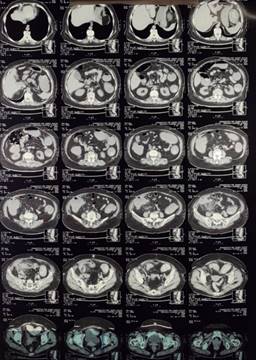

Paciente femenina de 66 años con antecedente personal de importancia de diabetes tipo 2, de 40 años de evolución, tratada con insulina, así como hipertensión arterial sistémica, de 25 años de evolución, tratada con IECA; antecedente quirúrgico de reparación de hernia umbilical hace 14 años, cesárea hace 34 años y fractura de clavícula hace dos años. Es admitida al servicio de urgencias por presentar dolor abdominal localizado en la fosa iliaca derecha, el dolor abdominal era crónico, con más de seis meses de evolución; lo había presentado pero había cedido. La semana anterior comenzó con dolor abdominal localizado en fosa iliaca derecha el cual cedía con medicamentos, asimismo síntomas de oclusión intestinal sin poder canalizar gases y no presentó vómito. A la exploración se encontró taquicardia, irritación peritoneal en fosa iliaca derecha, tumoración palpable en fosa iliaca derecha de alrededor de 7 × 10 cm y peristaltismo muy disminuido. Se le realizó una tomografía abdominal (Figuras 1 y 2) donde se observó una tumoración que se encontraba con probable perforación, lo mencionan como probable apendicitis complicada vs tumoración. Se decide realizar laparotomía exploradora encontrando líquido de reacción inflamatorio no purulento de aproximadamente 100 cc, se observa tumoración que depende del ciego tomando sigmoides, por lo que se decide practicar hemicolectomía derecha con ileostomía y cierre de cabo distal, así también se realiza resección del sigmoides de alrededor de 7 cm, realizando anastomosis de sigmoides término-terminal con técnica manual con sutura no reabsorbible. Se colocan drenajes cerrados hacia corredera derecha y drenaje cerrado a hueco pélvico. Se extraen piezas de patología y se envían. Se termina el procedimiento quirúrgico, pasa a recuperación y posteriormente a piso, se le indica ayuno por 24 horas y comenzamos con dieta enteral. La evolución es hacia la mejoría clínica, comienza gasto por estoma, siete días posterior a la cirugía se retiran los drenajes sin complicaciones, se refiere a servicio de Infectología quien da ciclo de antibiótico a base de tetraciclinas por seis semanas. El reporte de patología demuestra región de hemicolectomía (Figura 3) sin alteraciones del tejido linfoide en placas de Peyer, en la serosa se encuentran depositadas pseudomembranas de fibrina con neutrófilos. La válvula ileocecal y mucosa cecoascendente demuestran reacción inflamatoria mixta con numerosos piocitos que se extienden al tejido adiposo del mesoapéndice que alberga colonias bacterianas de Actinomyces spp. que conforman filamentos ramificantes y coronas radiales formando gránulos de azufre (Figura 4). El apéndice cecal demuestra periapendicitis aguda fibrinopurulenta y el tejido de sigmoides con pronunciado edema en sus paredes. Diagnóstico: Actinomyces invasor cecal, perforado con peritonitis aguda fibrinopurulenta secundaria. La paciente es vista en servicio de consulta externa de cirugía general con evolución favorable. Infectología recomienda esperar por lo menos seis meses libres de actividad inflamatoria y de tratamiento médico con antibiótico para planear la reconexión intestinal.

Figura 2: Tomografía abdominal donde se aprecia tumoración cecal que se pudiera confundir con un absceso por apendicitis aguda.